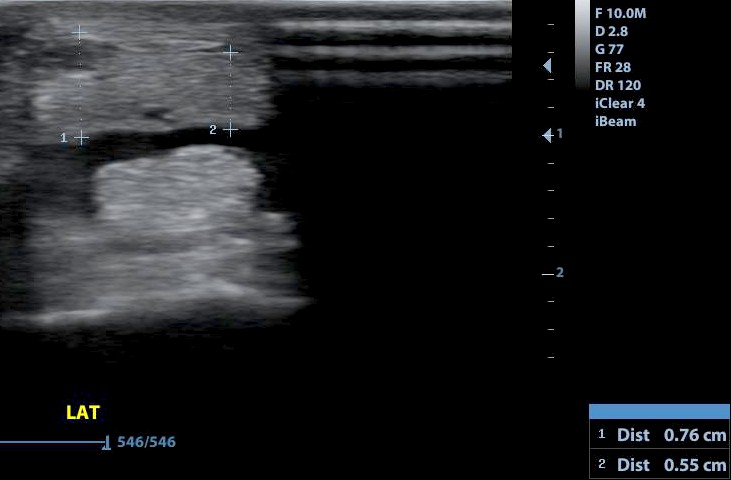

A mérések azt mutatják, hogy a sérült bal oldal jelentősen megvastagodott az ép oldalhoz viszonyítva. Fontos az aszimmetrikus alak felismerése is!